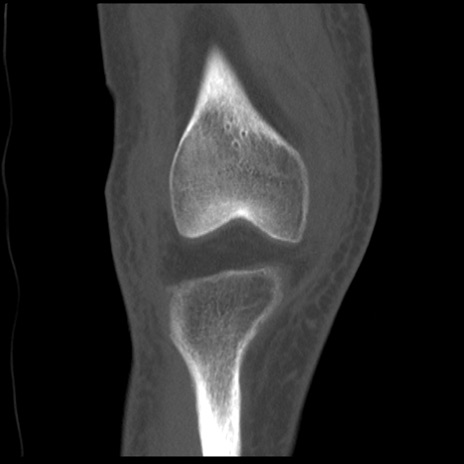

症例28 右膝関節CT(冠状断像)

右膝関節CT

矢状断像